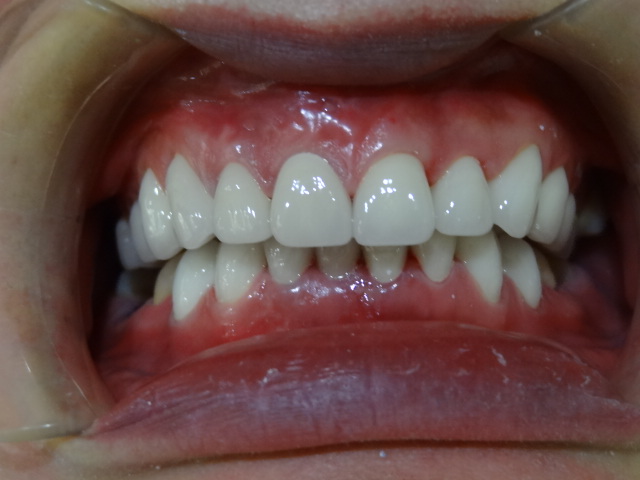

術(shù)后

做完超聲波洗牙第二天,牙齒還是有酸酸的感覺,不過牙齒真的白了很多,看起來干凈了不少,走在路上我時不時傻笑,女朋友以為我傻了,哈哈!

超聲波洗牙第二天效果